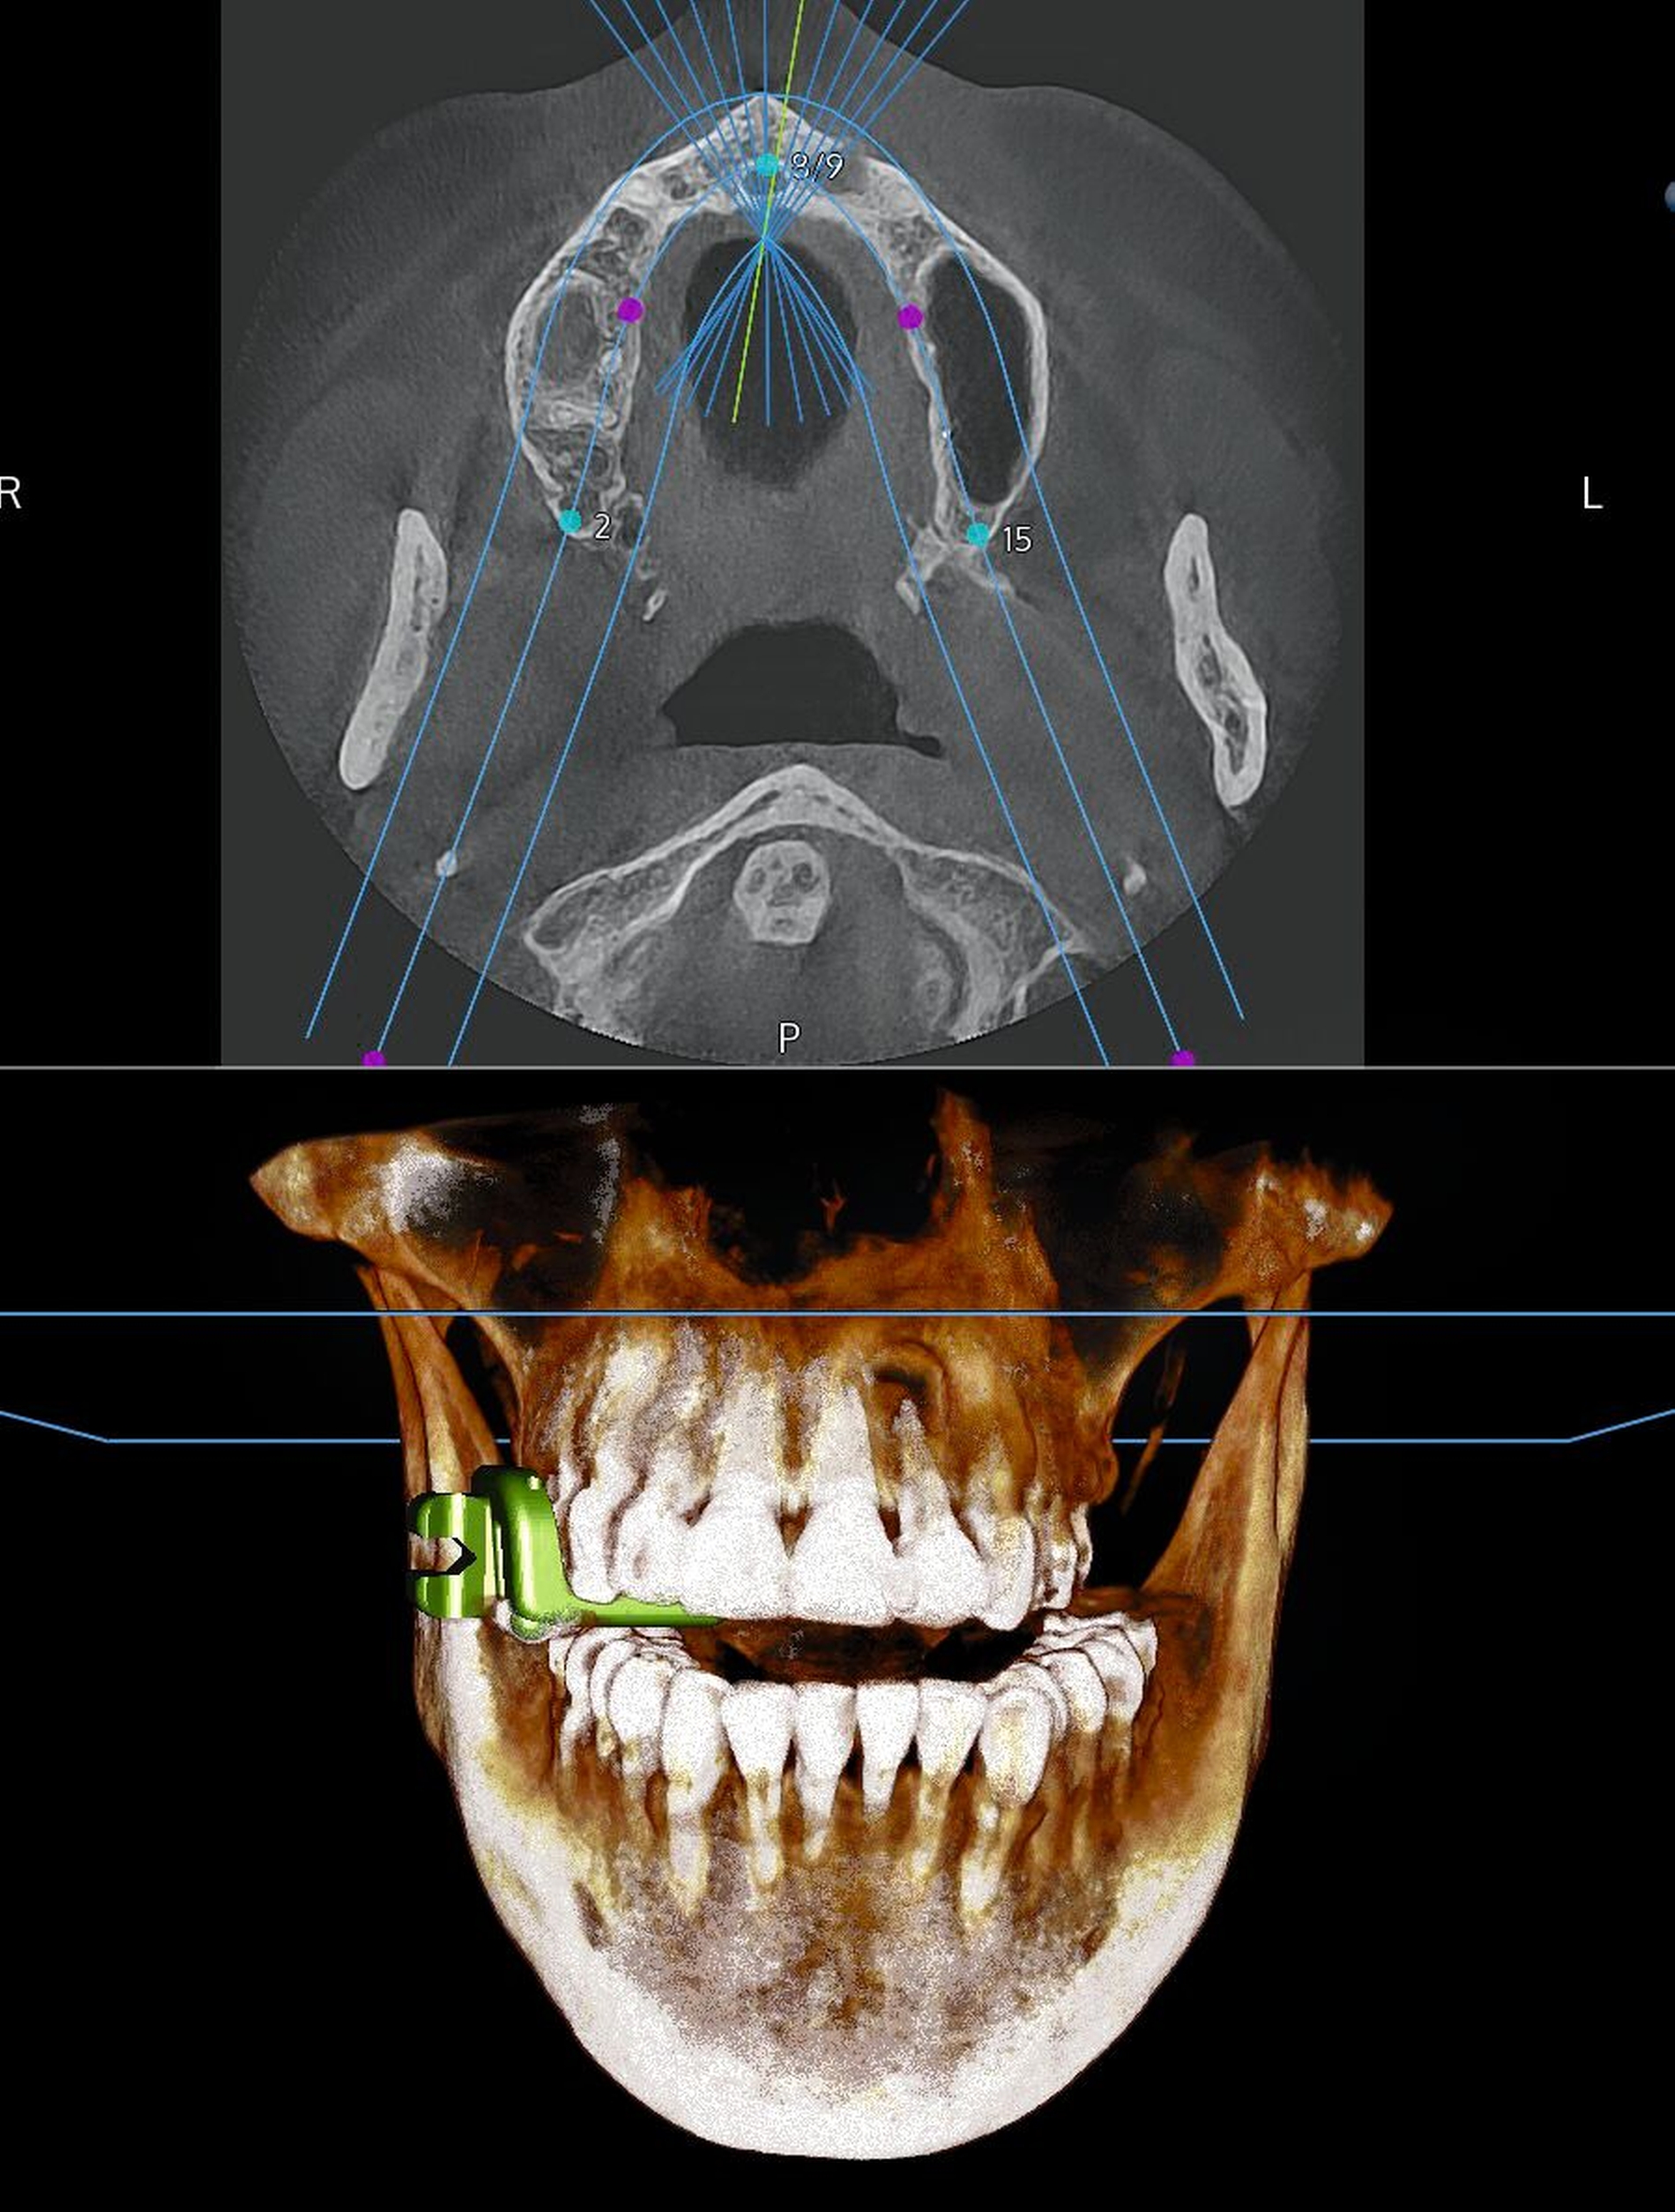

Die dreidimensionale präoperative Planung zeigte, dass das Wurzelkanalinstrument in der palatinalen Wand der linken Kieferhöhle eingebettet war (Abbildung 2a). Um intraoperativ die Mess- und Distanzfunktionen des Navigationssystems optimal nutzen zu können, wurde ein „Simulationsimplantat“ virtuell so geplant, dass der Fremdkörper zentral beziehungsweise apikal im Verlauf des geplanten Implantatkörpers lag (Abbildung 2b).